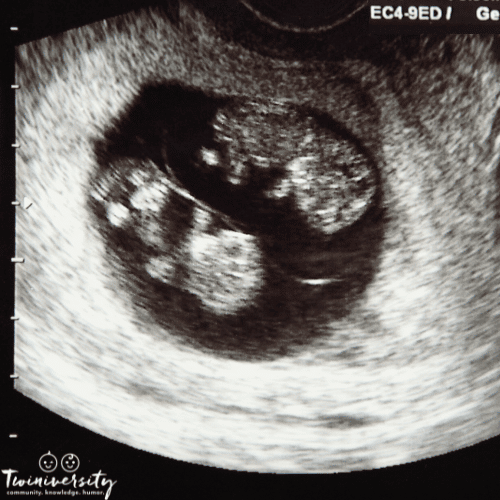

Your doctor will do an ultrasound to determine the chorionicity (how many placentas) and amnionicity (how many amniotic sacs) of your twins. This is important as monochorionic twins require different prenatal care than dichorionic.

Frequent Ultrasounds and Monitoring

The number one way to ensure a safe and healthy identical twin pregnancy is with frequent ultrasounds. Current guidelines recommend ultrasounds every two weeks starting at 12 weeks for mono-mono twins and at 16 weeks for mono-di twins. These scans monitor growth, fluid levels, and blood flow. You may receive extra anatomy scans as your doctor monitors for weight and growth discordance.